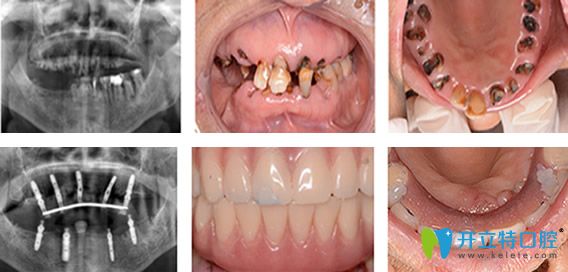

1950后 / 程阿姨

職業(yè):單位退休職工       癥狀:全口牙缺失

需求:種一口好牙檢查與診斷:牙槽骨缺損嚴(yán)重

種植方案:牙槽骨骨量修復(fù),德國ICX全口種植

主診醫(yī)生:劉旭光

種植牙過程及結(jié)果展示:

70歲老太在珠江口腔種植牙過程及結(jié)果展示